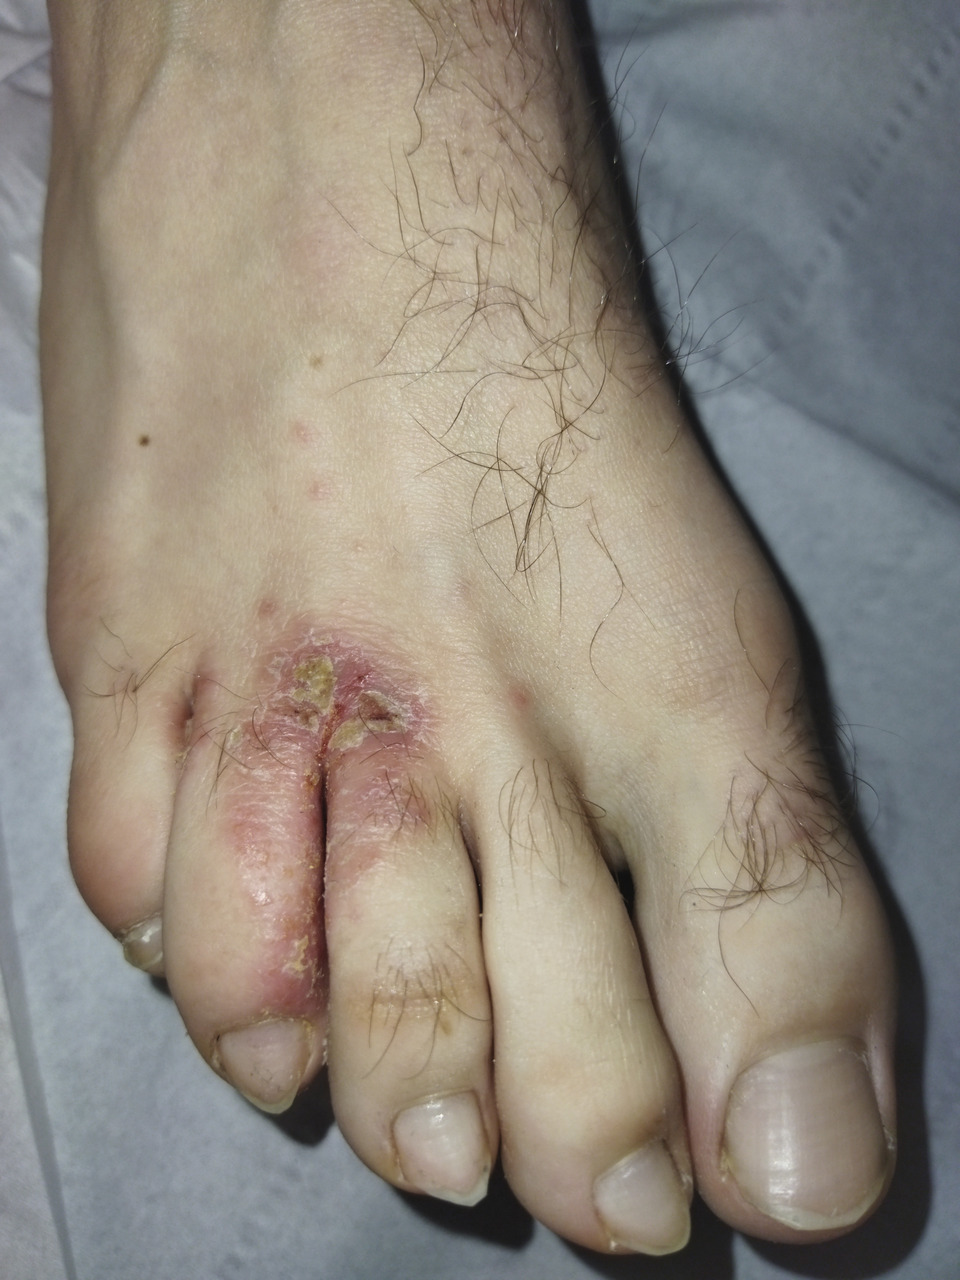

Maxime, militaire de 20 ans, se plaint d’une lésion prurigineuse entre le 3e et le 4e orteil. Apparue depuis plusieurs semaines, elle s’étend progressivement.

L’examen clinique objective un intertrigo avec une extension sous les orteils adjacents. On remarque des croûtes mélicériques sur la face dorsale de la lésion, et le fond de l’intertrigo est fissuré, évoquant une candidose.

Cliniquement, la lésion est érythémateuse, avec des croûtes mélicériques et associée aux signes cliniques classiques de la pathologie sous-jacente.